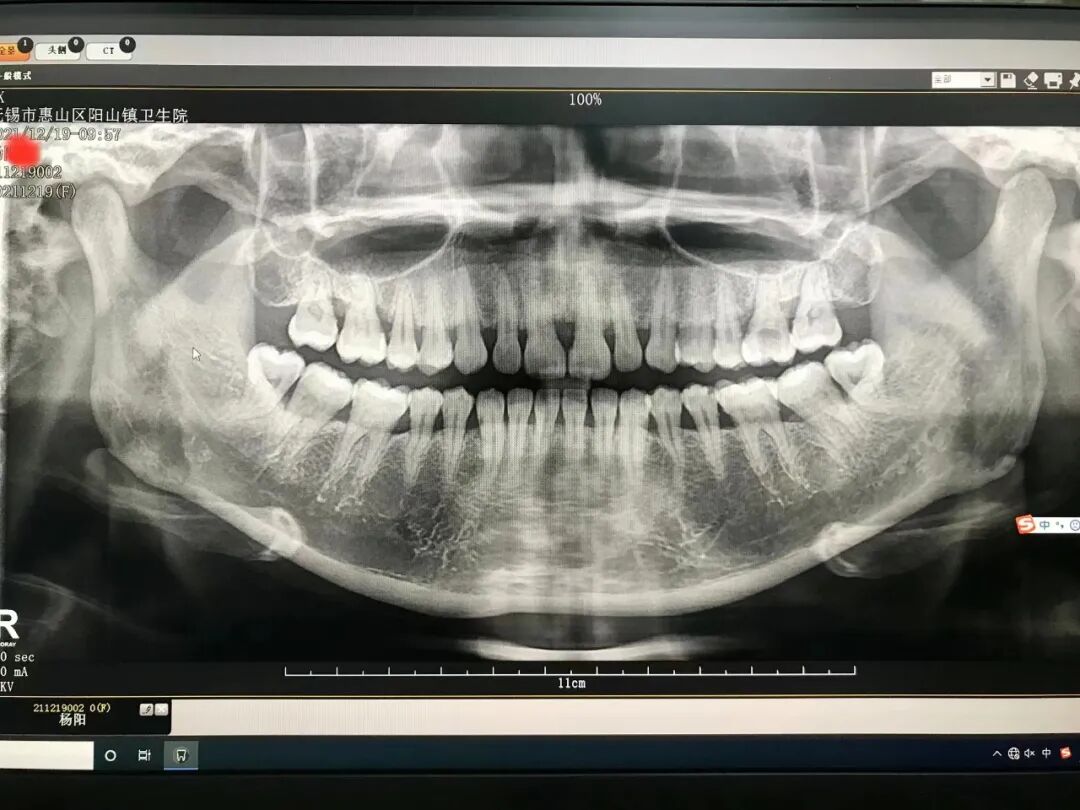

口腔ct怎么拍摄口腔全景CT落户阳山镇卫生院,看牙更精准、更高效_https://www.jmylbn.com_新闻资讯_第4张上图为我院口腔全景CT拍摄的牙片,明显精准度更高,更有利于满足口腔诊疗的临床需求。

通过对比,传统二维的牙片因重叠影、伪影等原因扭曲变形,无法准确给出病变的位置以及与近牙的临接关系,而全新口腔CT可以拍出最清晰的图像,重建速度快,一次扫描即可获得全口腔双牙列三维立体影像。不仅如此,微光技术也会让更多患者收到更低的辐射剂量